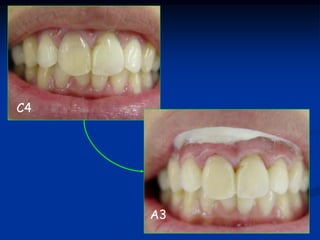

Clareamento em Dentes Despolpados

Clareamento Externo

Peróxido de Hidrogênio 35%

forma gel

Clareamento Interno

Peróxido de Carbamida 37%

Oxigênio Ativo

C4

A3

Clareamento Caseiro – Home Bleaching

MIRANDA et al.,2002

Clareamento Externo Peróxido deHidrogênio 35% forma gel Clareamento Interno Peróxido de Carbamida 37% forma gel

C4 A3

Clareamento Caseiro –Home Bleaching MIRANDA et al.,2002